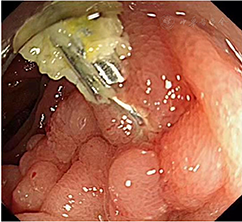

诊疗过程:入院后针对患者间断性便血,给予抑酸、止血、输血、补液、支持等治疗后便血未见明显缓解。入院后第3天急诊行SBE检查示:十二指肠及空肠近段肠腔内见大量鲜红色血液,进镜至空肠距幽门约1.5 m未发现出血灶(图1A)。退镜,冲洗、吸引观察,于空肠上段发现一大小为0.5 cm×0.5 cm的浅表凹陷性溃疡,缺损中间有血管走行,表面可见凝血块附着(图1B),且有搏动性出血,无明显炎性改变,考虑为Dieulafoy溃疡(图1C)。注射硬化剂止血(图1D)并联合钛夹止血(图1E、F),确认出血停止后结束治疗。术后继续辅以输注悬浮红细胞,并进行抑酸、保护胃黏膜、调节肠道菌群等综合治疗。术后腹部X线平片示钛夹位于空肠上段(图2),腹部增强CT未见明显异常。患者的病情逐渐平稳要求出院回家休养。1个月后复查SBE,Dieulafoy溃疡完全愈合,两枚钛夹残留(图3),继续随访7个月未再出现便血症状。

注:A示十二指肠及空肠近段肠腔内见大量鲜红色血液,B示退镜,冲洗、吸引观察,于空肠上段发现一浅表凹陷性溃疡伴凝血块附着,C示溃疡表面无炎性改变,见搏动性出血,D示注射硬化剂止血,E、F示钛夹止血

注:1个月后复查单气囊小肠镜示Dieulafoy溃疡完全愈合